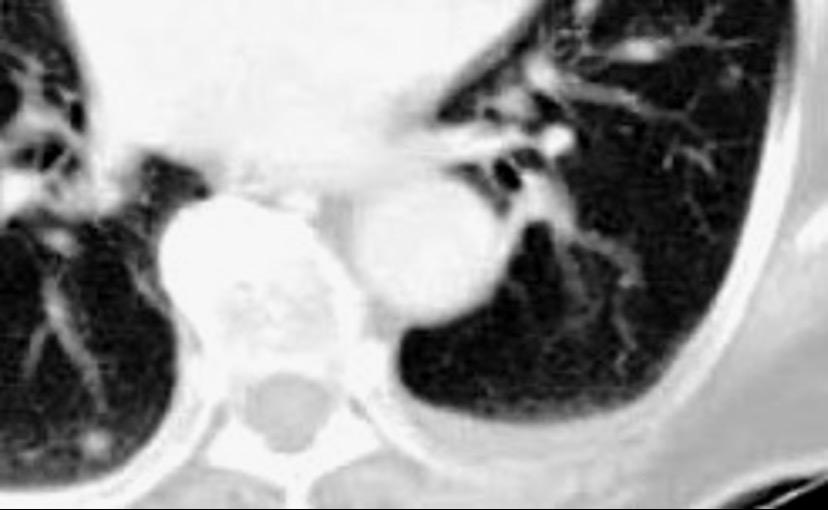

Signo de la Pleura separada “Split pleural sign”

Capas pleurales de grosor uniforme realzadas por el contraste

No específico de empiema. Indica “exudado”. 68% de pacientes con empiema pleural.

Capas pleurales de grosor uniforme

Realce grasa extrapleural (30%)

> Grasa Extrapleural. (60-80%)

Kraus GJ. Split pleural sign. Radiology 2007